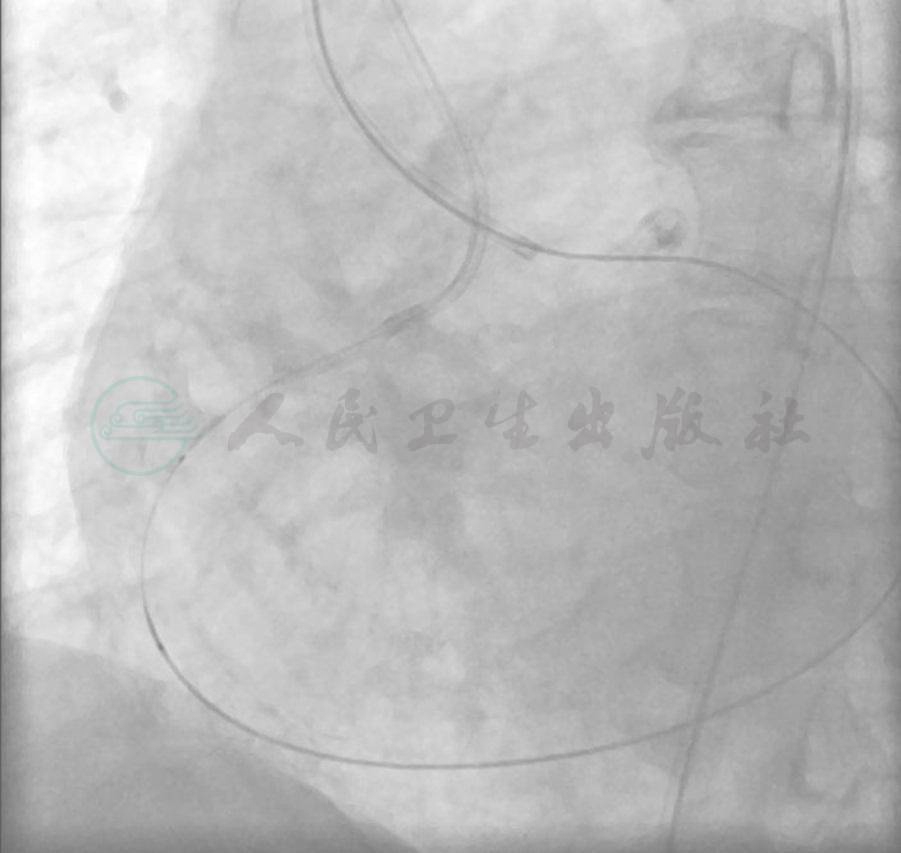

图10 更换为Fielder FC导丝后顺利逆向通过LCX左向右侧支进入RCA

图11 更换为Fielder FC导丝后顺利逆向通过LCX左向右侧支进入RCA

图12 更换为Fielder FC导丝后顺利逆向通过LCX左向右侧支进入RCA